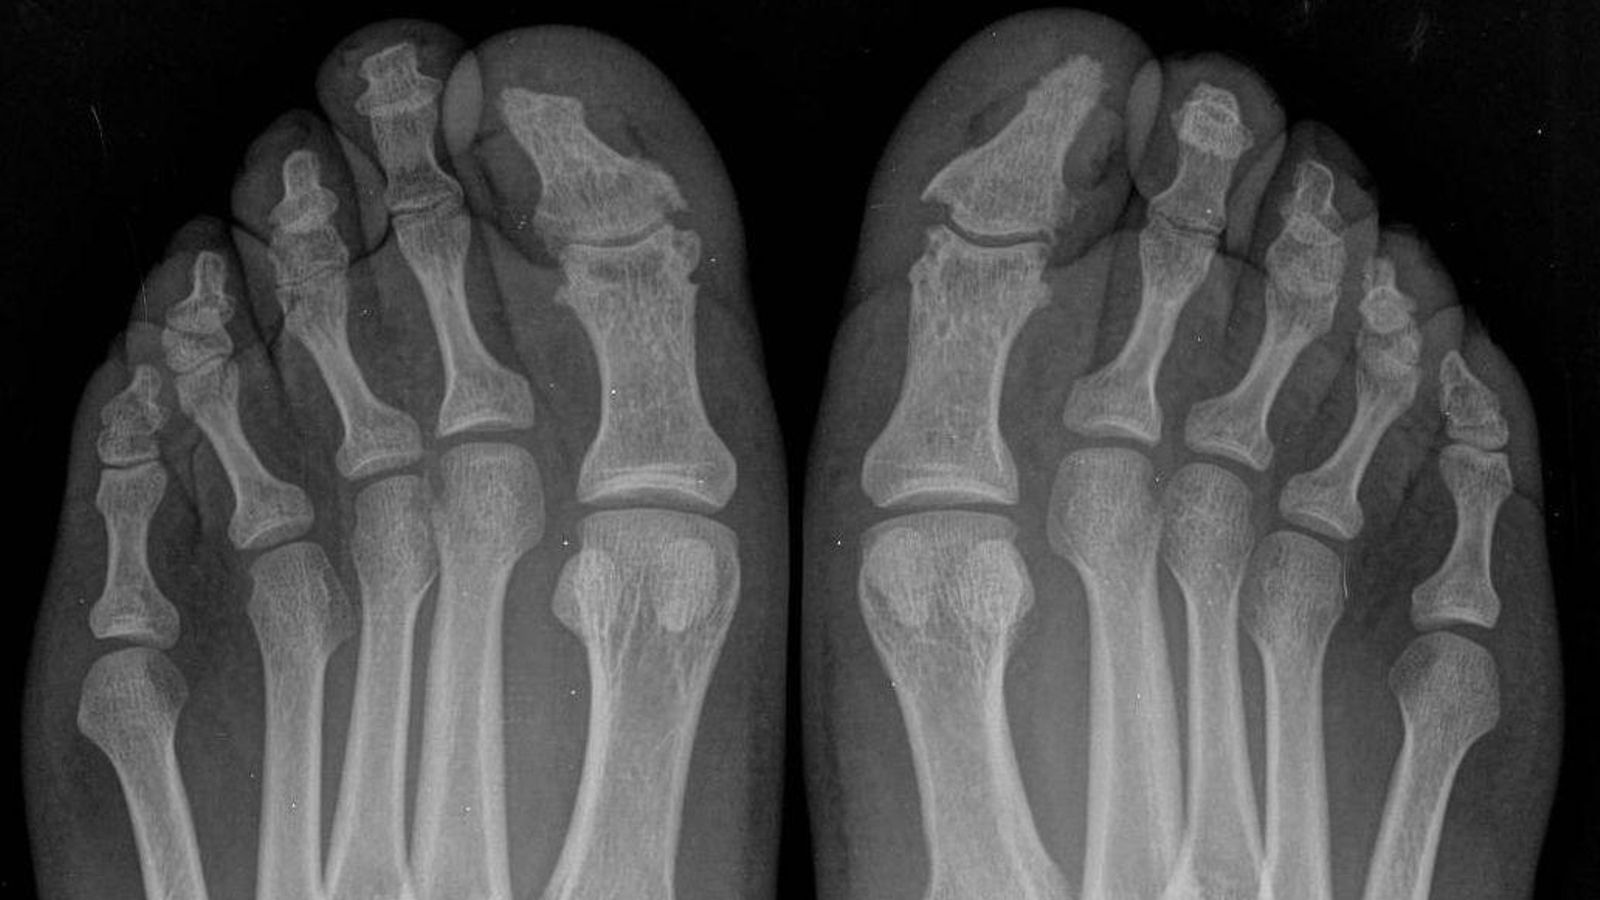

Afectación osteo-articular de la enfermedad en ambos pies.

Afectación osteo-articular de la enfermedad en ambos pies. / H. U. V.